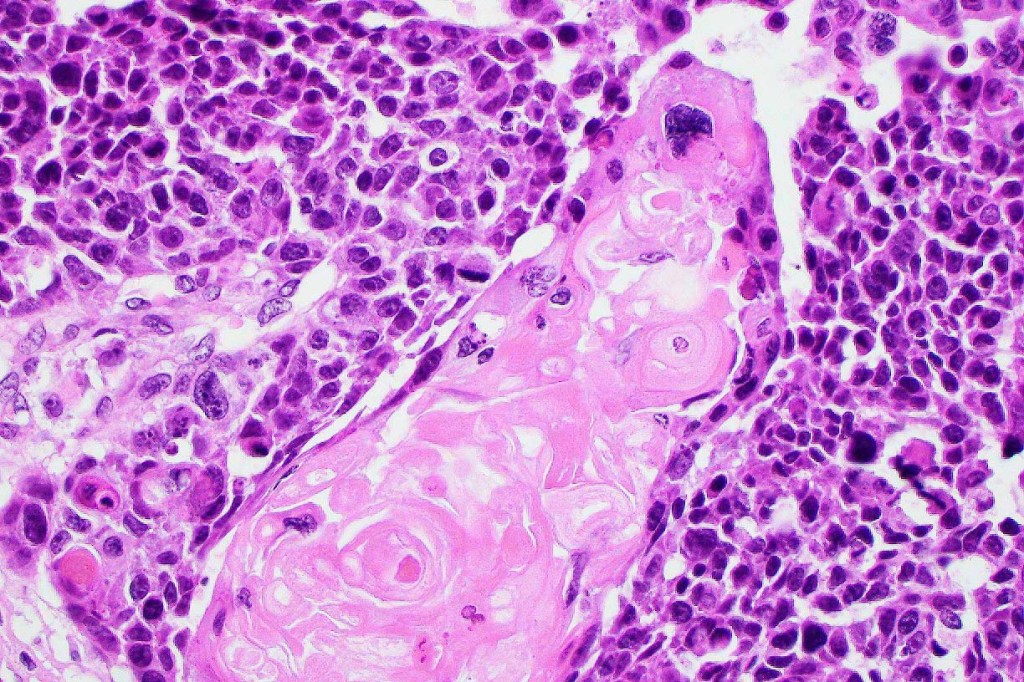

•Lobular or a diffusely infiltrating growth pattern. Composed of pleomorphic hyperchromatic, basaloid cells with nucleolar prominence, abundant mitoses & atypical mitoses (brisk mitotic activity should not be used as a defining feature of matrical carcinoma since in the evolving phase mitoses are typically very numerous in pilomatricoma)

•Necrosis common

•Matricial & supramatricial differentiation

•Squamous differentiation